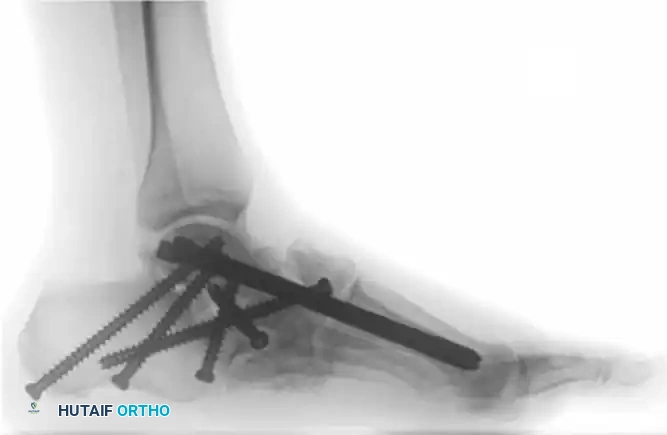

The following preoperative and postoperative radiographs demonstrate the successful application of augmented fixation in a young diabetic patient with a severe bimalleolar fracture-subluxation:

FIGURE 85-25 A and B: Preoperative radiographs of a highly unstable bimalleolar ankle fracture-subluxation in a 19-year-old man with a 12-year history of insulin-dependent diabetes mellitus.

FIGURE 85-25 C-E: Postoperative fixation demonstrating robust fibular plating, medial malleolar screw fixation, and critical supplemental syndesmotic screws to reinforce the mortise.